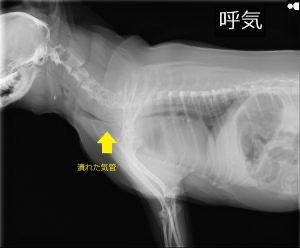

急いでかかりつけの動物病院に連絡をとり連れて行くと先生が緊急で対応してくださり、レントゲンを撮った結果、気管虚脱と診断されました。

気管虚脱とは、空気の通り道である気管を円形に支える軟骨が生まれつき柔らかいことで、気管が潰れて息ができなくなる病気です。

※ほさか動物病院様のホームページ https://www.hosaka-ac.co.jp/shorei/cat/kokyuki より引用しました。

※ほさか動物病院様はかかりつけ病院とは関係ございません。

レントゲン写真等の掲載を病院にお願いしたのですが、以前何かの問題が起きたらしくSNSへの掲載は辞退して欲しいと言われましたのでマーチのレントゲンを載せる事が出来ません。